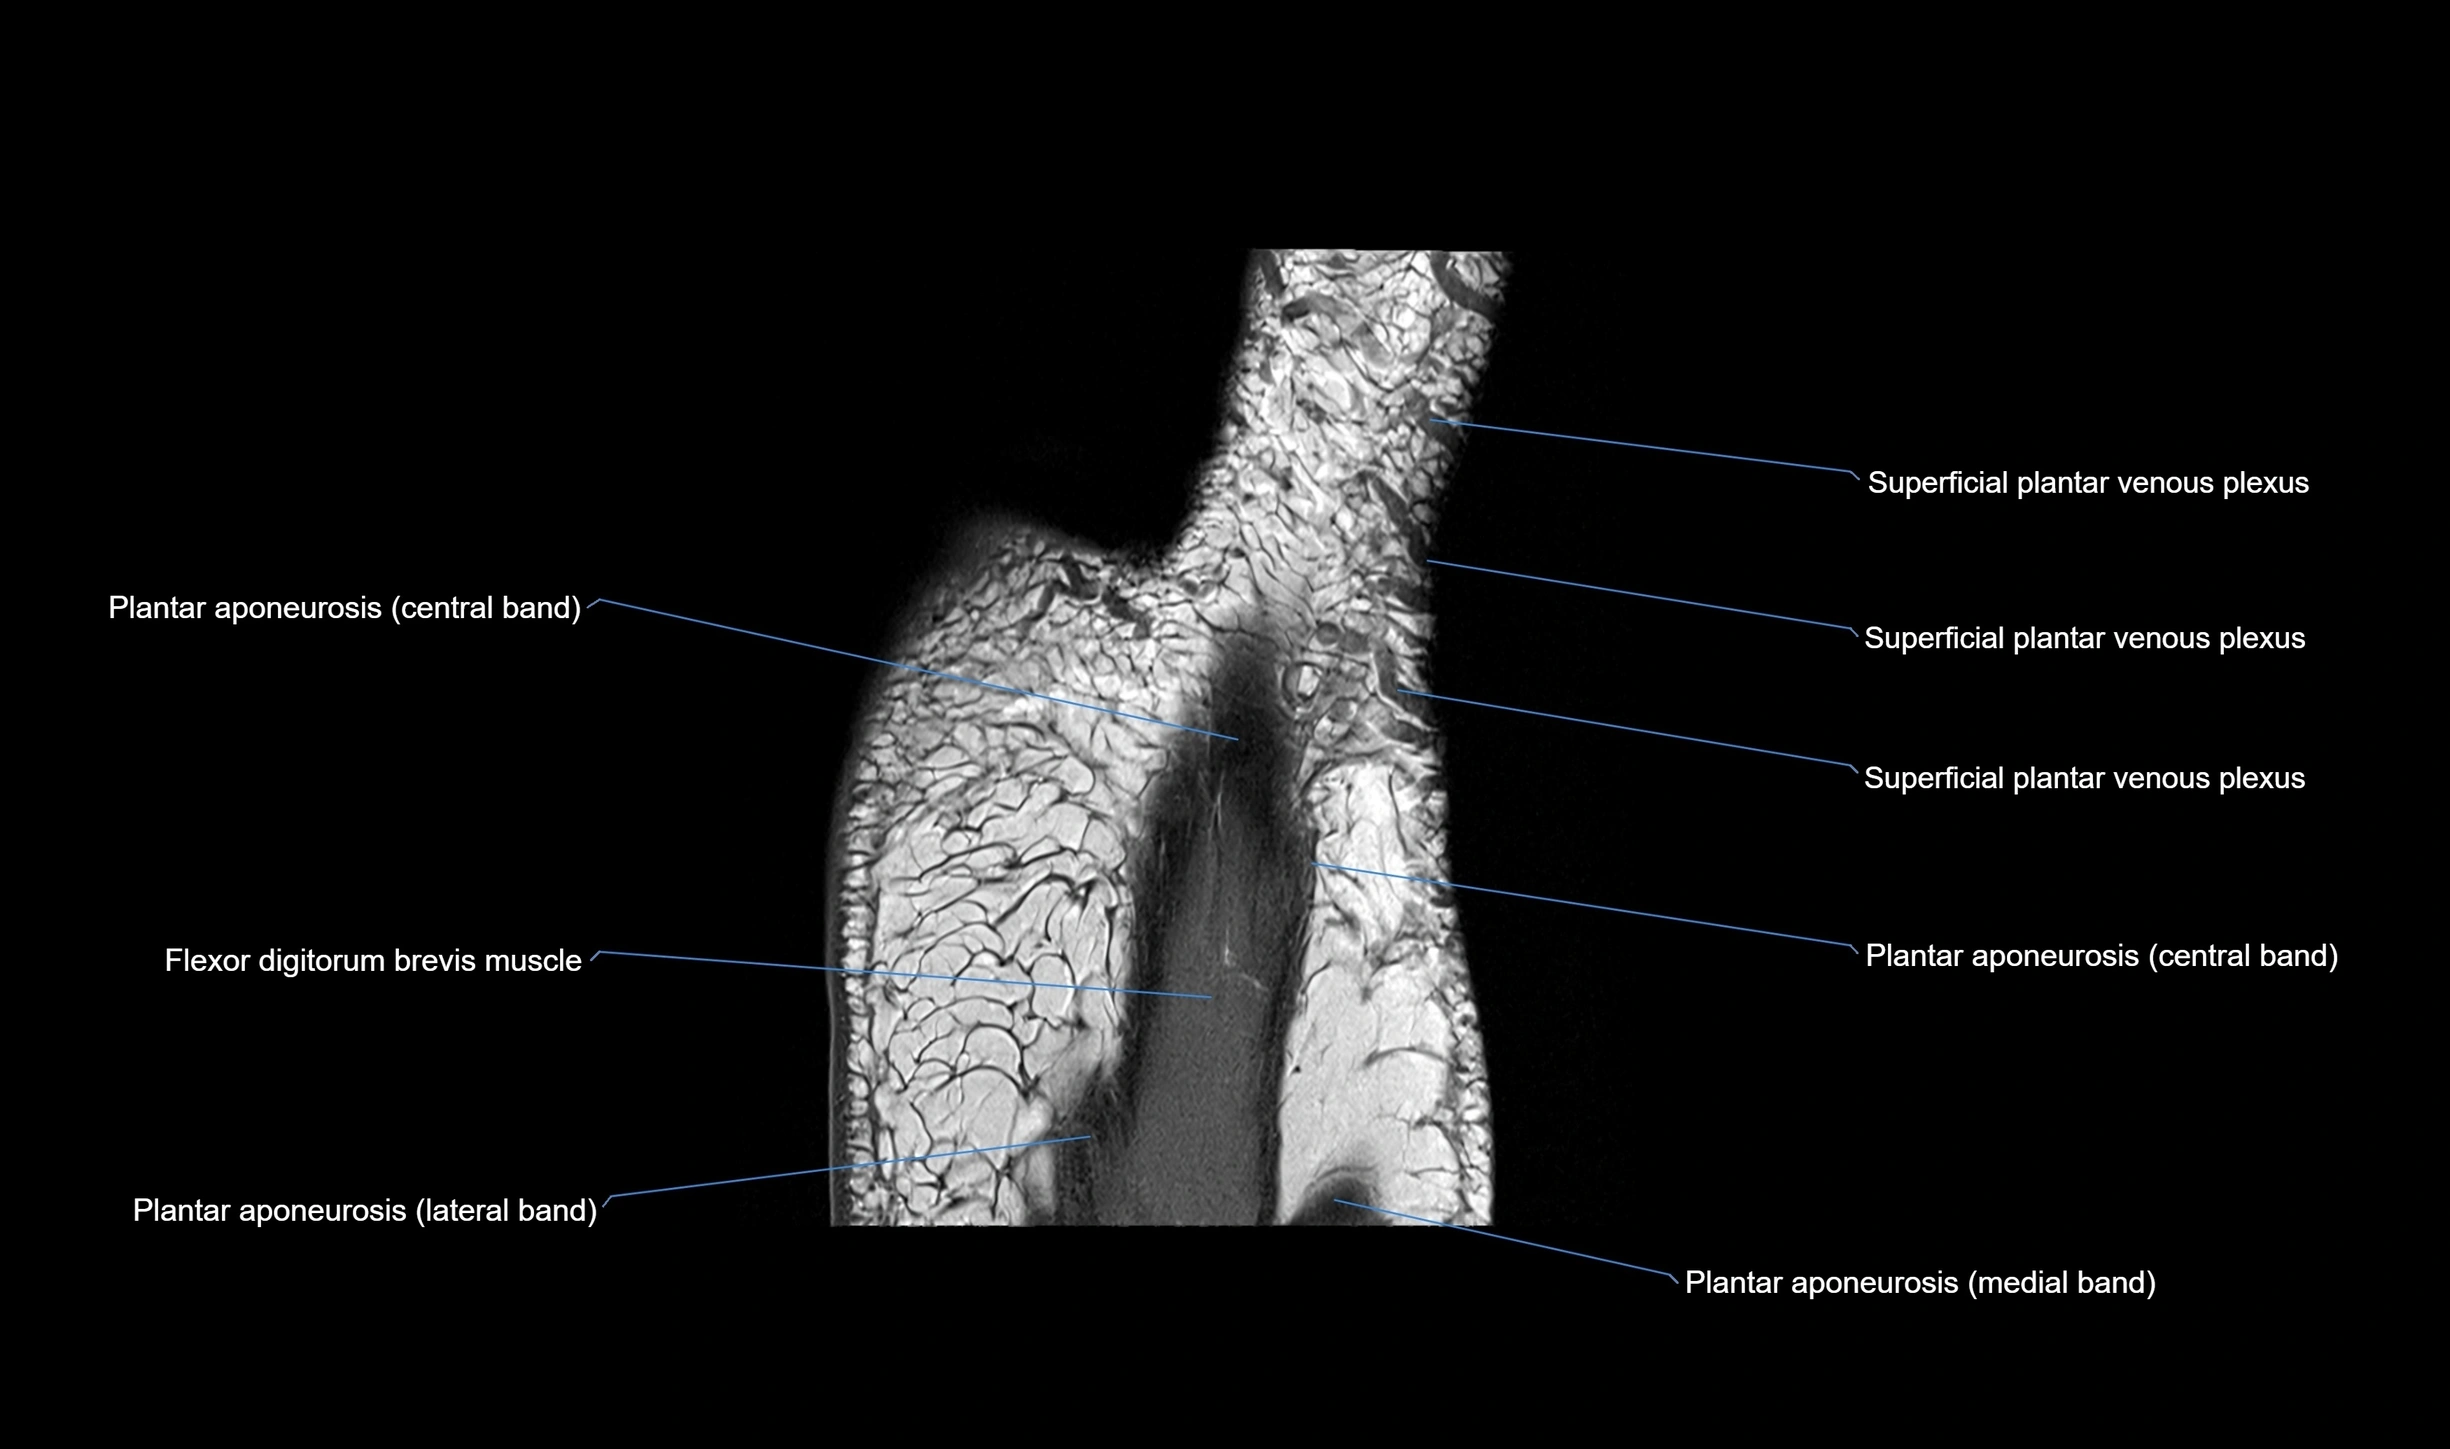

MRI image